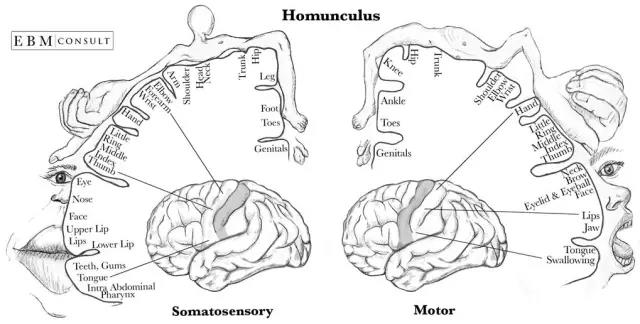

運動和軀體感覺皮層緊挨著對方,它們很有趣,因為它們已經被良好的映射出來了。神經科學家確切地知道每個部分連接到你身體的哪一個部分。于是就有了下面這張令人毛骨悚然圖:侏儒。

由先鋒神經外科醫生懷爾德·彭菲爾德創建的侏儒,在視覺上顯示運動和軀體皮層如何被映射。

運動和軀體感覺皮層緊挨著對方,它們很有趣,因為它們已經被良好的映射出來了。神經科學家確切地知道每個部分連接到你身體的哪一個部分。于是就有了下面這張令人毛骨悚然圖:侏儒。

由先鋒神經外科醫生懷爾德·彭菲爾德創建的侏儒,在視覺上顯示運動和軀體皮層如何被映射。